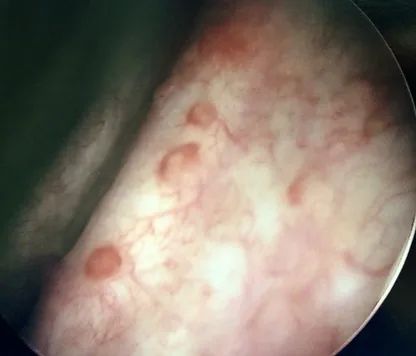

A hormone-secreting tumour that can occur in the adrenal glands. Phaeochromocytomas usually develop in the small glands on top of the kidneys (adrenal glands). They most commonly affect people between the ages of 20 and 50, but can occur at any age. Because of hormones secreted, symptoms include high blood pressure, sweating, rapid heartbeat and headache. Surgery to remove the tumour is usually required.